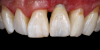

(30.) Smile, retracted, and close-up views of the provisional restoration at the 4-month follow-up appointment to assess the development of tissue volume and contours. Note that most of the open gingival embrasures have filled with papillae and that the gingival zenith exhibits excessive volume.

Figure 30

(31.) Smile, retracted, and close-up views of the provisional restoration at the 4-month follow-up appointment to assess the development of tissue volume and contours. Note that most of the open gingival embrasures have filled with papillae and that the gingival zenith exhibits excessive volume.

Figure 31

(32.) Smile, retracted, and close-up views of the provisional restoration at the 4-month follow-up appointment to assess the development of tissue volume and contours. Note that most of the open gingival embrasures have filled with papillae and that the gingival zenith exhibits excessive volume.

Figure 32

(33.) Retracted view with the teeth apart and close-up view of the definitive screw-retained zirconia restoration in position (Definitive restoration fabricated by Sam Alawie and Beverly Hills Dental Lab).

Figure 33

(34.) Retracted view with the teeth apart and close-up view of the definitive screw-retained zirconia restoration in position (Definitive restoration fabricated by Sam Alawie and Beverly Hills Dental Lab).

Figure 34